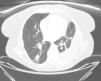

Spontaneous hemothorax is a very rare form of presentation of bronchogenic carcinoma. We present the case of a 73-year-old woman, non-smoker, with a history of hypertension, dyslipidaemia, diabetes mellitus, psoriasis and depressive disorder. The patient attended the emergency department with a one-week history of pleuritic chest pain and two-month history of weight loss and asthenia. Physical examination revealed absence of breath sounds in the base of the left hemithorax. The chest radiograph showed a radiopaque image in the left base consistent with pleural effusion and contralateral mediastinal shift. Computed tomography (CT) was performed, in which loculated pleural effusion, atelectasia of the lower lobe and lingula, and a solitary pulmonary nodule (maximum 2cm in diameter) were observed in the apical segment of the right lower lobe (Fig. 1). Thoracentesis was subsequently carried out, in which hemothorax was diagnosed and treated with chest drainage. The follow-up radiograph showed expansion, so the drain was removed on the sixth day. A new CT scan was then performed in which complete resolution of the hemothorax was observed, with persistence of the previously described nodule. The presence of malignant cells suggestive of adenocarcinoma was observed in 2 pleural fluid cytology specimens. Immunohistochemical analyses were positive for MOC-31, and a polymerase chain reaction (PCR) study showed a mutation in exon 19 of the EGFR gene. The patient was discharged with a diagnosis of EGFR-positive large cell carcinoma and treated with gefitinib.